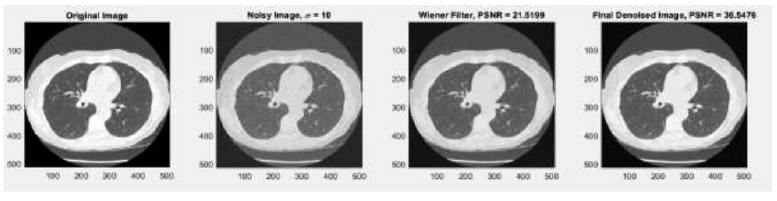

Fig. (4a) illustrates the original clean CT images. The clean CT image was corrupted by adding Gaussian noise, as represented in Fig. (4b), with various noise variances (σ = 5, 10, 15, 20). This addition of Gaussian noise leads to blurriness in the clean CT image.

In the context of the wiener filter, the method noise-based approach evaluates performance using PSNR, which shows good results, no new artifacts are generated, and fine detail preservation is done effectively at noise variance σ = 5 (before method noise PSNR =26.7258 dB, after method noise PSNR =36.0159), σ=10 (before method noise PSNR = 21.5199 dB, after method noise PSNR = 36.5476dB), σ = 15 (before method noise PSNR =18.4166 dB, after method noise PSNR =36.8506 dB), and σ =20 (before method noise PSNR =17.1852, after method noise PSNR = 36.3446 dB) (Tables 1-4).

Outcomes of the impact of wiener-filter without and with method noise-based CT image denoising using CNN with noise variance (σ=10).